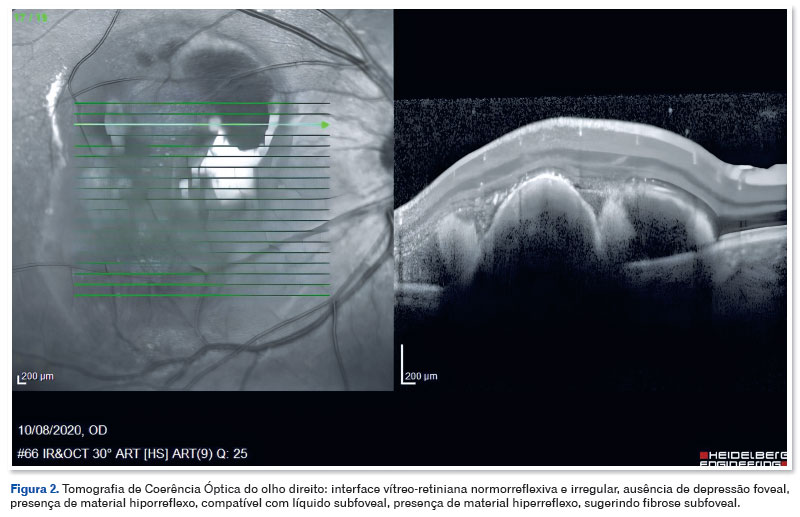

Homem, 39 anos, portador de DM1, diagnosticado na primeira infância por meio de teste PCR com eletroforese capilar e southern blot que identificou repetições patológicas da trinca CTG no gene DMPK, relatou perda de visão recente no OD. Ao exame oftalmológico, a acuidade visual (AV) era 20/100 em OD e 20/20 em OE, ambas com correção. A biomicroscopia revelou conjuntiva clara, córnea transparente, ausência de reação na câmara anterior e cristalino transparente em ambos os olhos. Movimento ocular extrínseco preservado em ambos os olhos. O mapeamento da retina evidenciou hemorragia sub-retiniana em área macular, associada a exsudação em olho direito (Figura 1). O paciente não apresentava alterações retinianas no olho esquerdo. A angiografia fluoresceínica incluiu alguns achados como hipofluorescência por bloqueio na área macular do olho direito. O exame de tomografia de coerência óptica (OCT) evidenciou interface vítreo-retiniana normorreflexiva e irregular, ausência de depressão foveal, presença de material hiporrefletivo, compatível com líquido subfoveal e presença de material hiperreflexivo, sugerindo fibrose subfoveal (Figura 2).